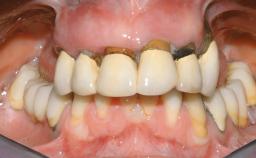

Immediate Loading of Eight Implants in the Maxilla and Six Implants in the Mandible and Final Restoration with Three-Unit and Four-Unit FDPs

Extensive scientific evidence has confirmed that immediately loaded implants with fixed full-arch provisional restorations can osseointegrate with success rates similar to conventionally or delayed loaded implants. A number of immediate-provisionalization techniques for edentulous jaws have been described. Some protocols differ when it comes to prefabricated provisional templates versus complete denture conversion; intrasurgical impressions versus direct relining; and cemented versus screw-retained provisional restorations. In this context, complete-denture conversion has been proposed for either intrasurgical impressions or direct relining. Another possibility is the utilization of a prefabricated provisional to be adapted either in the mouth (by direct relining) or in the laboratory (on a working model obtained from an intrasurgical impression).

Prosthesis Type FDP

Defining Characteristics Fully edentulous upper jaw to be rehabilitated with an implant-borne fixed dental prosthesis

Loading Protocol Immediate